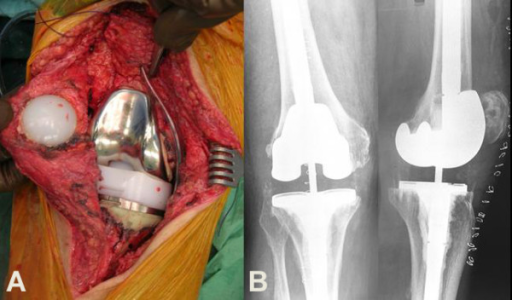

Total joint arthroplasty is a successful surgical operation, which has gained acceptance worldwide in the last few decades. Arthroplasty is a surgical technique, which replaces all articulating degenerated natural surfaces with artificial materials, with the aim of achieving pain relief and improved joint mobility.

Artroplastia total de cadera | Artroplastia total de rodilla | Artroplastia total de hombro | Artroplastia parcial Total hip arthroplasty | Total knee arthroplasty | Total shoulder arthroplasty | Partial arthroplasty